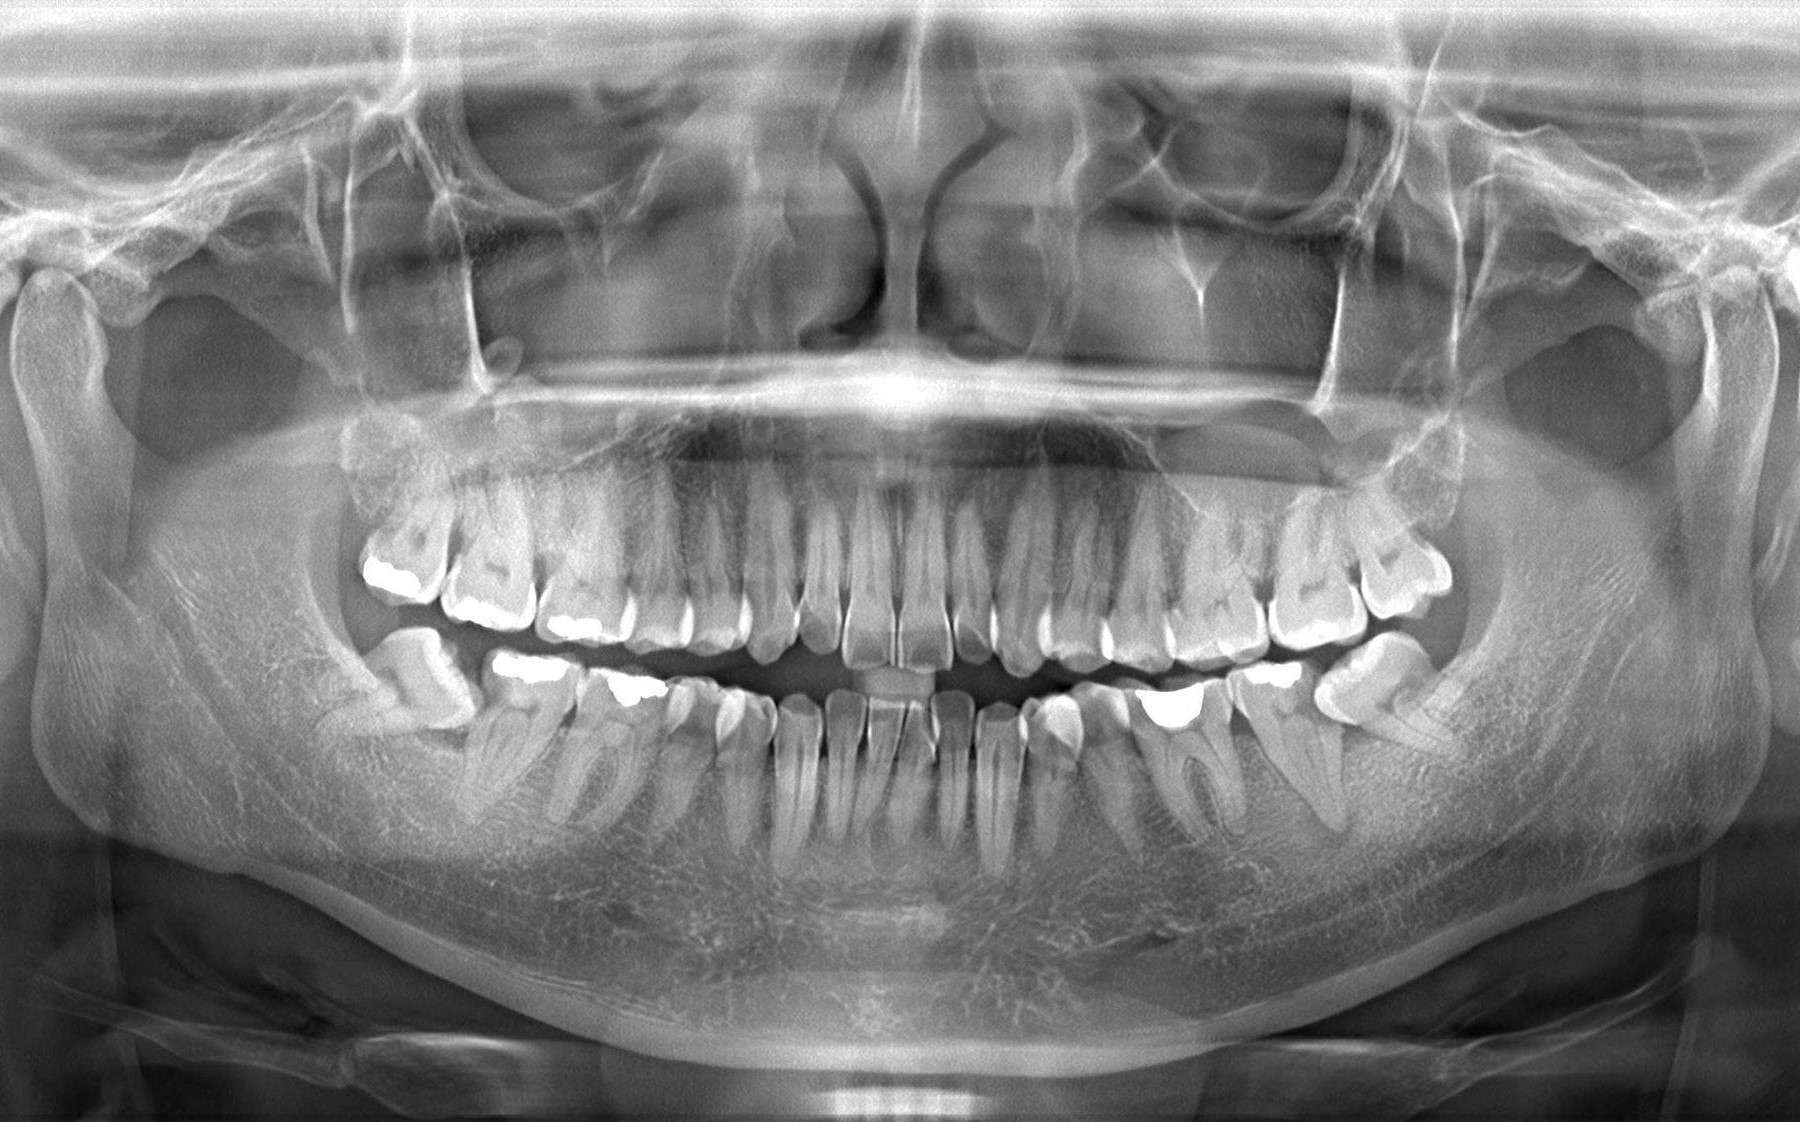

👉 Trước khi nhổ răng khôn, bác sĩ sẽ:

-

Chụp phim X-quang hoặc CT

Xác định vị trí chính xác của răng và dây thần kinh

Lựa chọn phương án nhổ an toàn

Thăm khám và chụp phim đánh giá

Kiểm tra tổng quát răng miệng

Chụp phim X-quang hoặc CT (nếu cần)

Đánh giá hướng mọc răng, chân răng, vị trí dây thần kinh